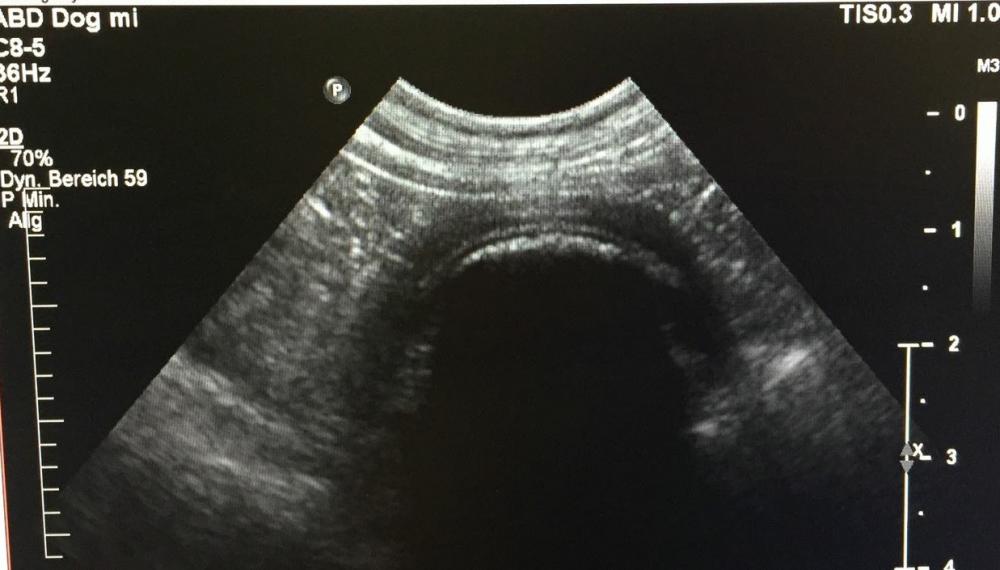

Sie wurde mit einer Schwäche der Hintergliedmaßen vom Haustierarzt ans Kleintierzentrum überwiesen. Nach Röntgen und Ultraschall stand fest, das die Schwäche nur sekundär zu einem Fremdkörper im Bauch des Hundes vorlag. Dieser war bereits vom Magen in den Dünndarm gewandert und verursachte einen Ileus (lebensbedrohlichen Darmverschluss). Aura's Blutwerte zeigten bereits einen massiven Flüssigkeitsverlust und erhöhte Entzündungszellen an, sodass es sich hier nicht um ein orthopädisches, sondern ein chirurgisches Problem handelte und sofort operiert werden musste.